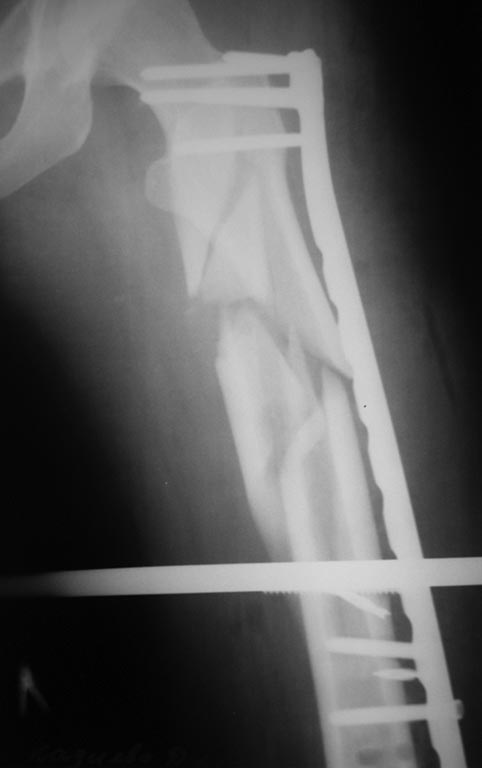

проходило у нас. Кости таза фиксированы канюлированными винтами и АВФ.

Предполагался БИОС бедренной кости, однако из-за отсутствия в больнице

современных имплантов (угадайте с 3-х раз- почему?)и средств у больной

был выполнен 22.01.14 малоинвазивный остеосинтез проксимального отдела

бедра чем Бог послал (каким-то чудом оказавшаяся у нас дистальная

бедренная пластина "Деост", не б/у) (см. снимки)-критика принимается.

Рекомендации она не соблюдала: нагрузку на ногу начала недели 3 назад.

Сейчас беспокоят боли в одноименном коленном суставе, отека нет, болей в

месте перелома нет, анализы в норме, незначительное ограничение движений

в ТБС. По месту жительства выполнила КТ (снимки и описание в

приложении). Местные коллеги утверждают, что необходимо сделать